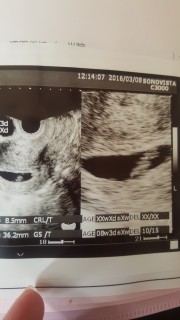

最終月経から6w6dになりますが、月経周期が25日なので、実際には7w3dになるかも知れません(*^^*) 2度の流産を経験しての自然妊娠!! CRL8.9mmで順調に成長中との先生のお話でした(*^^*) 今回の検診では、元気な心音も聞く事が出来て凄く嬉しかったです(*^^*)

体温、排卵検査薬を使っての自己計算では6w6dですが計測では6w0d。上の子は予定日算出に4日ワープしたりしてたので自己計算とは多少ズレが生じるものなんですね。心拍確認できたのでとりあえず今日のところは一安心している次第。 1w以降に再診して予定日出してもらい、母子手帳もらいにいけます。 胎嚢20.7mmで胎芽8.7mm。